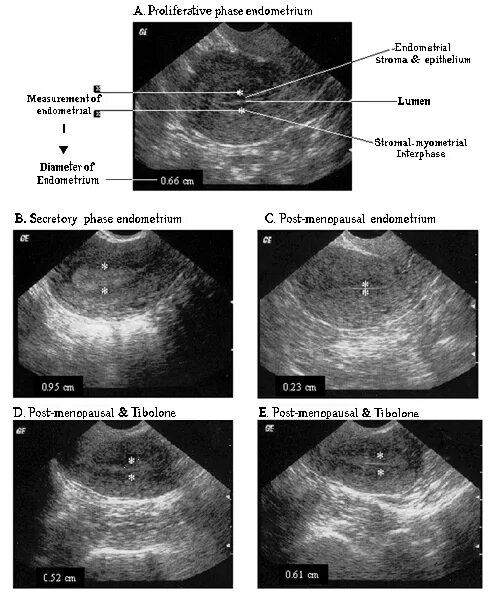

Эндометрий второй фазы цикла